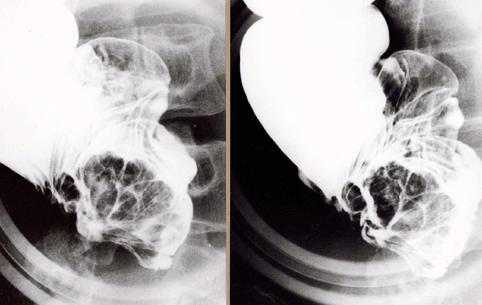

대장암과 유사한 형태를 나타낸 상행결장의 염증성 종괴

Tokyo Pref., 국림암센터 중앙병원과 큐슈암센터의 공동작성

[Image-ID:511]

종양양 병변/기타

대장/회맹부

X-P